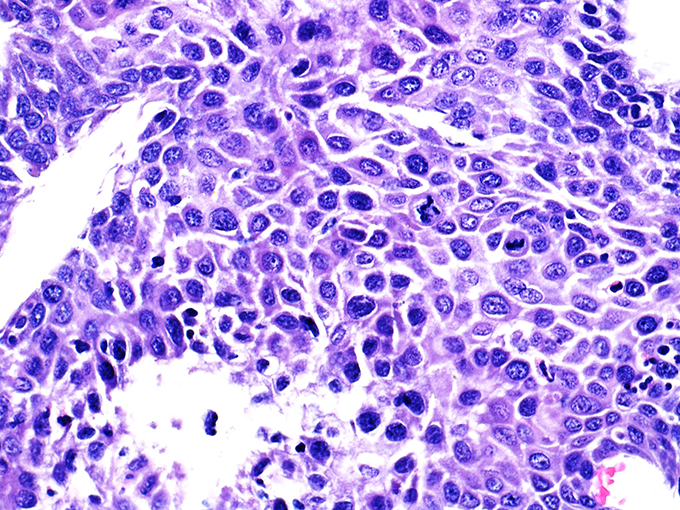

Case 1

Area 1 - Soft Bx CIN 2 40x - High Power |